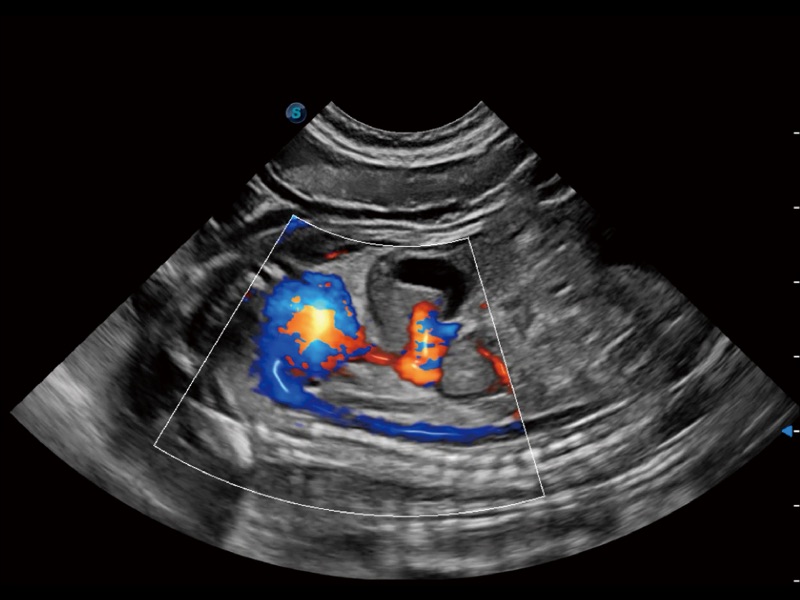

(犬)胎儿主动脉弓立体血流